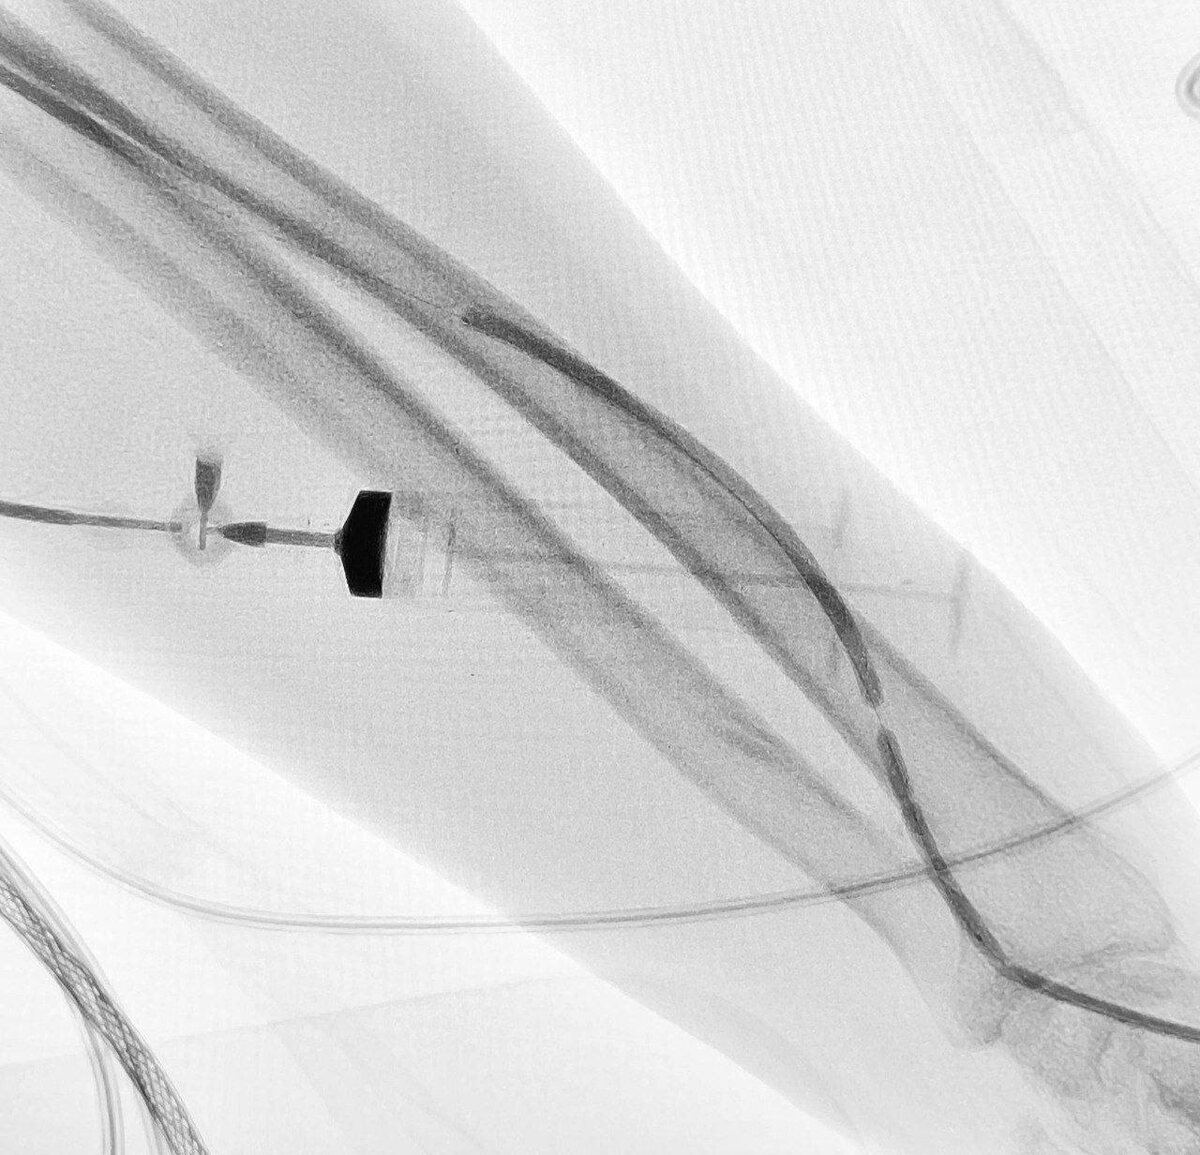

Эндоваскулярные хирурги МСЧ № 4 восстановили работу артериовенозной фистулы у пациента с тяжёлой почечной недостаточностью. Из-за тромба кровоток был полностью перекрыт, а значит — под угрозой оказался гемодиализ. 💉Врачи пошли по щадящему пути: через небольшой прокол под местной анестезией они провели катетер, устранили закупорку и расширили сосуд с помощью баллона. Всё — под рентген-контролем и без большой операции.🩻 👏Главное — диализ можно было возобновить сразу, без недель ожидания. Быстро, точно и максимально бережно для пациента. Фото: Министр здравоохранения Омской области

Эндоваскулярные хирурги МСЧ № 4 восстановили работу артериовенозной фистулы у пациента с тяжёлой почечной недостаточностью. Из-за тромба кровоток был полностью перекрыт, а значит — под угрозой оказался гемодиализ.

💉Врачи пошли по щадящему пути: через небольшой прокол под местной анестезией они провели катетер, устранили закупорку и расширили сосуд с помощью баллона. Всё — под рентген-контролем и без большой операции.🩻

👏Главное — диализ можно было возобновить сразу, без недель ожидания. Быстро, точно и максимально бережно для пациента.

Фото: Министр здравоохранения Омской области